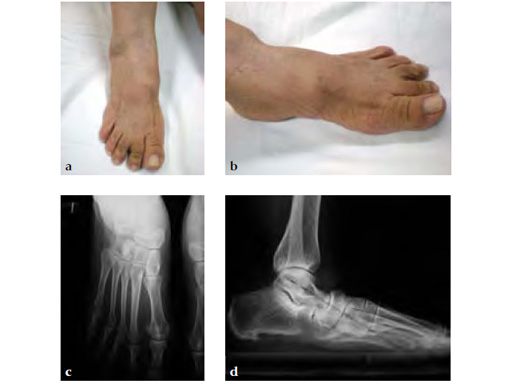

Case 1: 62-year-old white female with right stage II posterior tibial tendon insufficiency and II and III overload due to medial cuneiform first metatarsal joint instability treated with UCBL for 6 months after she complained of severe pain and increasing swelling

Case provided by Juan Bernardo Gerstner Garcs, Cali, Colombia

Stage II of her left posterior tendon dysfunction and tarso/metatarsal, instability visible on x-ray (see Fig 1a-c).